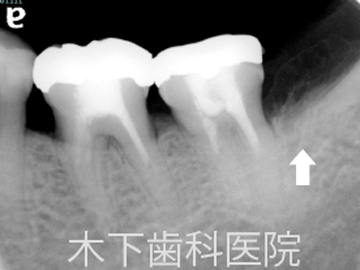

リグロスを用いた歯周組織再生療法症例

術後3年

歯周外科術後